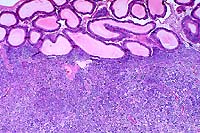

4x

obj

40x

- Case 16-4. Testis, Epididymis. Replacing seminiferous

tubules and extending around adjacent epididymal tubules, there

is an expansile, infiltrative mass consisting of sheets of polygonal

cells bearing pale granular, often vacuolated cells with oval

to round nuclei with granular basophilic chromatin.

20x

- Case 16-4. Testis. Seminiferous tubules are atrophic,

lack mature spermatozoa, and contain reduced numbers of spermatids.

Tubules are separated by clear space (edema) and free RBCs (hemorrhage).

- Case 16-4. Mesentary. Multifocally expanding mesothelium

lined adipose tissue, there are numerous irregularly sized nodules

of pleomorphic polygonal cells like those described above (metastatic

foci).

- AFIP Diagnoses:

- 1. Testis: Interstitial cell tumor, malignant, hedgehog,

insectivore.

- 2. Adipose tissue (omentum per contributor): Interstitial

cell tumor, malignant, metastatic.

- Conference Note: A densely cellular neoplasm has effaced

the testis and infiltrated the epididymis. It is composed of

polygonal cells arranged in broad cords, nests, packets and solidly

cellular areas, supported by a fine fibrovascular stroma. In

some areas, neoplastic cells palisade along the vascular stroma.

Neoplastic cells have indistinct cell borders, moderate amounts

of eosinophilic cytoplasm, and oval to elongate nuclei. Some

polygonal cells contain very distinct, clear, cytoplasmic vacuoles.

The mitotic rate is high, and some mitotic figures are bizarre.

Similar neoplastic cells are found within the submitted sections

of mesentery. Based on histomorphology, conference participants

agreed with the contributor's diagnosis. The differential diagnosis

that was considered included seminoma, Sertoli cell tumor, lymphoma,

mast cell tumor, and mesothelioma.